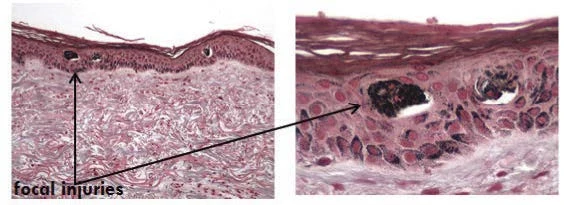

Клиническое гистологическое исследование кожи после воздействия пикосекундным александритовым лазерером, сплошным и фракционным методом

Результат:

Значительная абсорбция лазерного излучения меланином приводит к повреждениям меланин-содержащих эпидермальных клеток. Степень повреждений предположительно зависит от дозы излучения и уровня меланина, который связан с фототипом, загаром и меланиновым индексом (MI). Доставка излучения через фракционный оптический массив селективно повреждает локальные зоны эпидермиса, при этом имеет хороший профиль безопасности и эффективности.

Emil A. Tanghetti, MD

Через 10 минут: показаны вакуоли (полости) в эпидермисе, где произошла реакция лазер-индуцированного оптического разрушения после воздействия массивом FOCUS

Через 24 часа: протравливание меланина указывает на сфокусированные повреждения меланин-содержащих клеток, поражения ограничены эпидермальным слоем. Термических повреждений дермы не выявлено

Через 24 часа: стандартное H&E протравливание указывает на воспалительную реакцию дермального слоя, провоцирующую образование нового коллагена и эластина